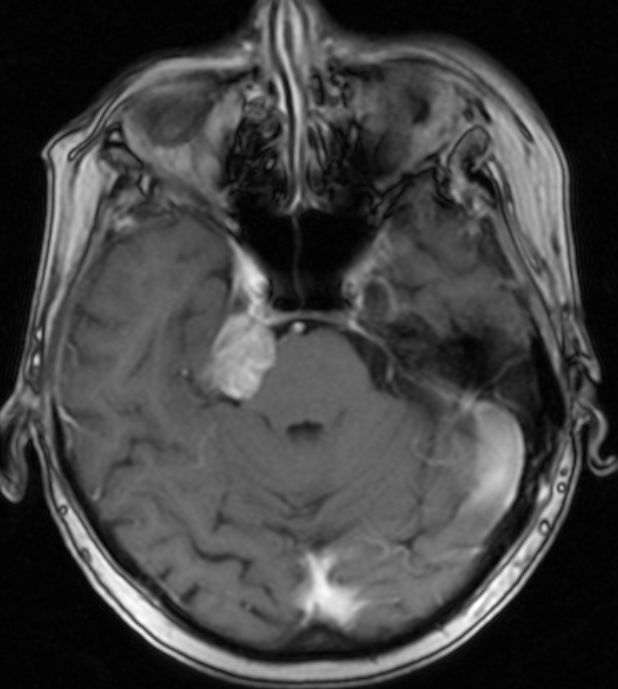

| Trigeminus - Neurom | 78-jährige Frau mit Trigeminusneuralgie seit 10 Jahren. Seit 8 Jahren gering größenprogredienter Tumor im rechten Kleinhirn-Brückenwinkel. | ||

![]() |

![]() ![]() | ||